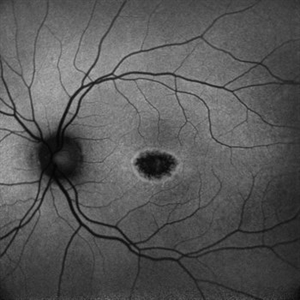

Heredomacular degeneration Heredomacular degenerationNov 30 2023 by Anjana Mirajkar, MS Ophthalmology Central autofluorescence image of RE of an 30 year old male in case of heredo-macular degeneration showing hypo fluorescence. Photographer: Dr. Anjana Mirajkar -Retina Foundation, Ahmedabad Imaging device: Mirante-Nidek Condition/keywords: heredomacular degeneration, HMD

Heredomacular degeneration Heredomacular degenerationNov 30 2023 by Anjana Mirajkar, MS Ophthalmology Central autofluorescence image of LE of an 30 year old male in case of heredo-macular degeneration showing hypo fluorescence. Photographer: Dr. Anjana Mirajkar -Retina Foundation, Ahmedabad Imaging device: Mirante-Nidek Condition/keywords: heredomacular degeneration, HMD